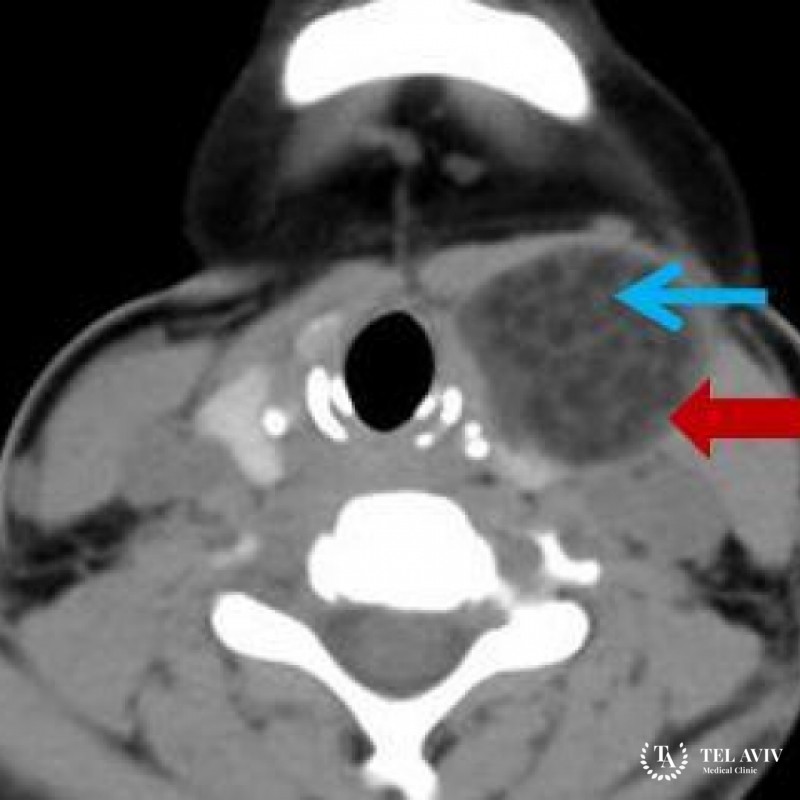

Дермоидная киста имеет схожие симптомы с некоторыми другими видами опухолей, поэтому перед назначением лечения ребенку обязательно проводится комплексная диагностику, которая может включать в себя: КТ с контрастом для уточнения размеров образования, его локализации, типа и содержимого, ультразвуковое исследование, пункция кисты. Уже после получения всей необходимой информации может быть назначена оптимальная тактика лечения.